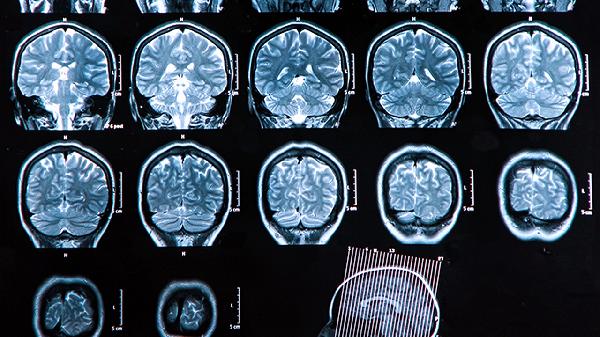

大脑前额叶功能受损可通过认知训练、有氧运动、正念冥想、社交互动、音乐疗法等方法改善。前额叶损伤可能影响决策、情绪控制、注意力功能,需结合个体情况选择干预方式。